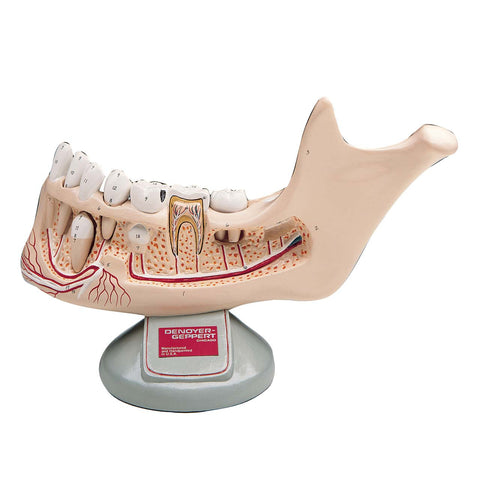

Anatomy

Anatomical models and charts by Body System or Anatomical Region for Nursing, Physical Therapy, and Medical Education.